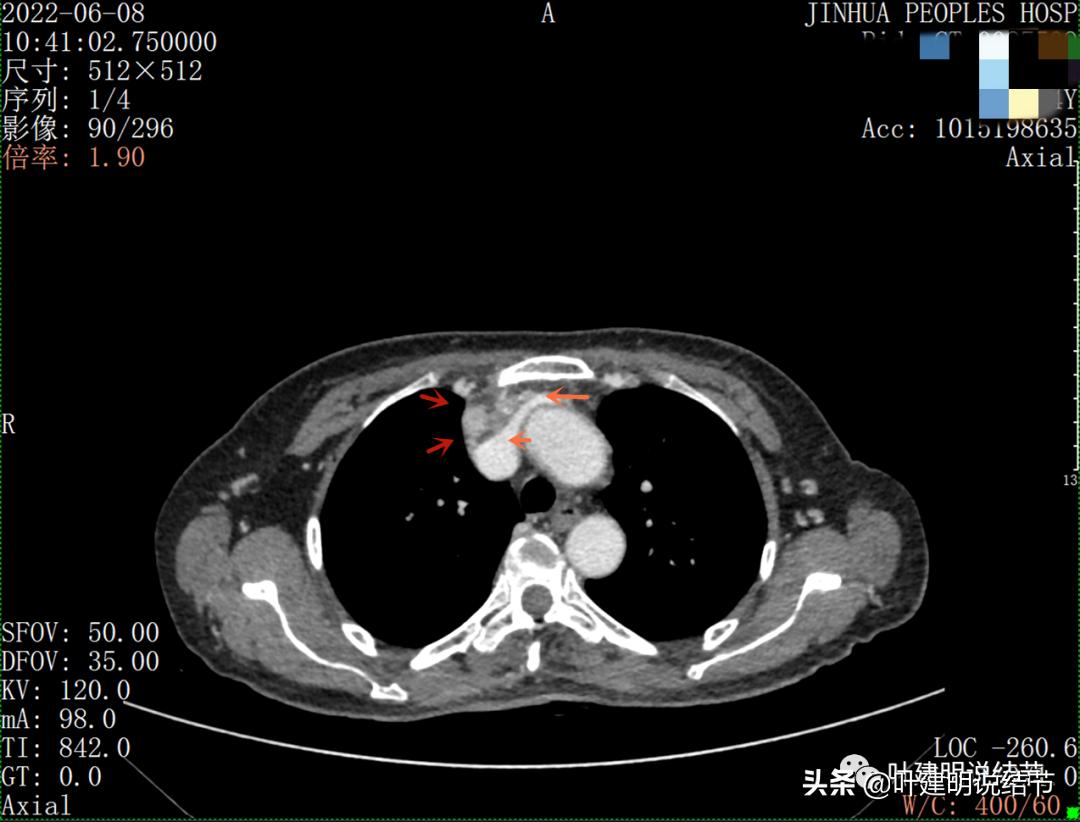

以下图片左侧是肺窗,右侧是纵隔窗。红色箭头示病灶,桔色箭头示无名静脉,黄色箭头示支气管,砖色箭头示上腔静脉,蓝色箭头示主动脉,紫色箭头示肺动脉。

病灶胸顶较高位置就出现了,在无名静脉水平

无名静脉略受压

特别显示与无名静脉的关系

上图示最大横断位达5厘米